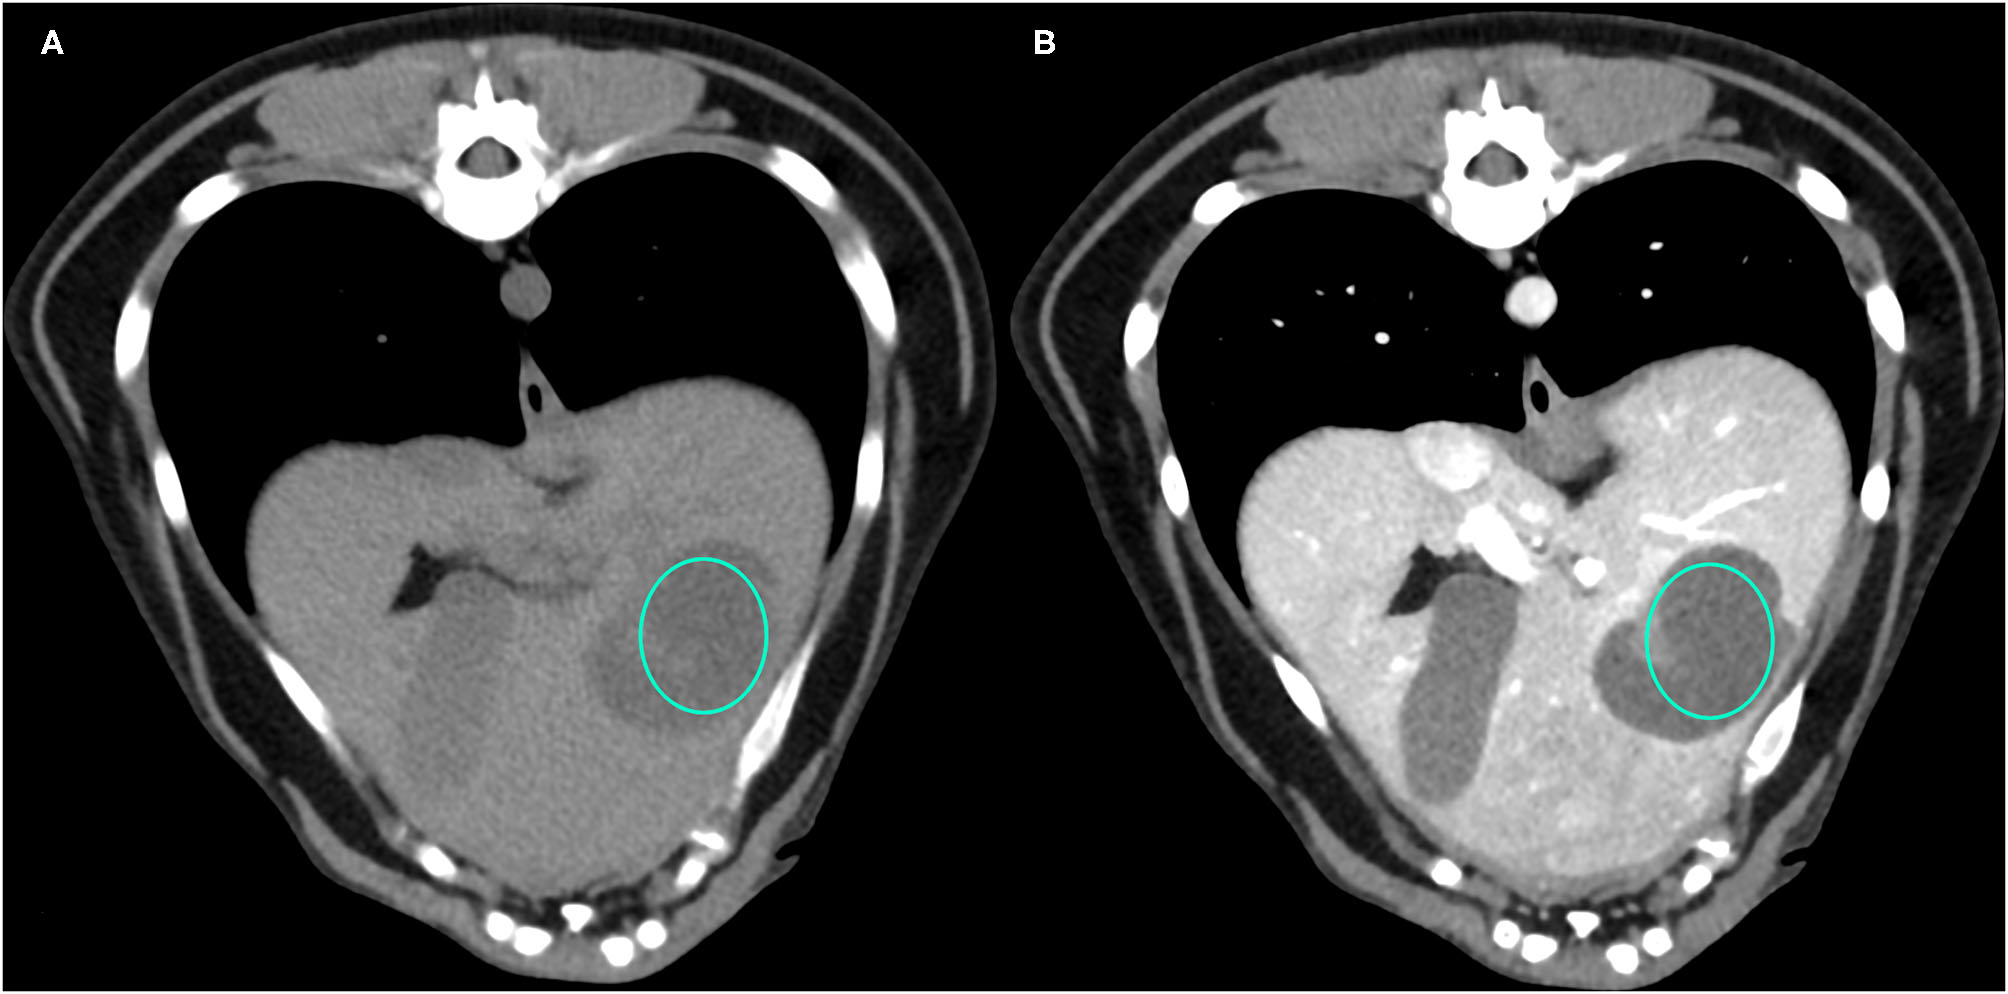

Figure 1

Example of a NH lesion that shows hypoattenuation and hypoenhancement, diffuse contrast enhancement pattern, with heterogeneous distribution, well-defined margins, irregular surface, and cyst-like appearance. (A) image obtained from the pre-contrast scan; (B) image obtained from the delayed scan. A ROI is placed inside the lesion in both. Based on the developed decision tree this lesion was classified as OBL.